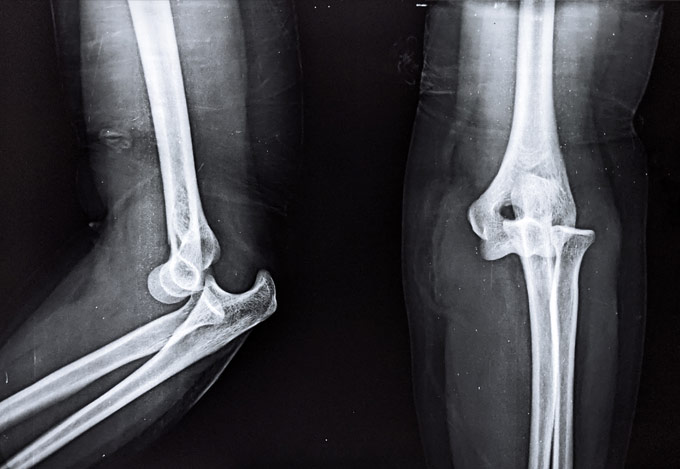

Έχει 5ετή μετεκπαίδευση και εργασία στο Ηνωμένο Βασίλειο ως ειδικός Ορθοπαιδικός Χειρουργός. Έχει εργαστεί στα Ορθοπαιδικά Τμήματα των Νοσοκομείων Southampton University Hospitals NHS Trust, Leeds Teaching Hospitals NHS Trust και στο Northampton General Hospital NHS Trust, με υποεξειδίκευση στη Χειρουργική Ώμου, Γόνατος, Ισχίου, Ποδοκνημικής & Άκρου Ποδός, Ώμου & Αγκώνος και Γενικού Τραύματος Ενηλίκων και Παίδων.

Κατά τη διάρκεια της εργασίας του στο Ηνωμένο Βασίλειο εκπαιδεύτηκε σε σύγχρονες τεχνικές Αρθροσκοπικής Χειρουργικής και Επανορθωτικής Χειρουργικής Ισχίου, Γόνατος και Ώμου. Επιπλέον έχει δώσει πολυάριθμες διαλέξεις και έχει εκπαιδεύσει νεότερους Ορθοπαιδικούς και φοιτητές Ιατρικής. Αξιοσημείωτο και πλούσιο είναι το επιστημονικό του έργο με συμμετοχή σε δεκάδες συνέδρια και σεμινάρια στην Ελλάδα και στο εξωτερικό και έχει πληθώρα προφορικών ανακοινώσεων και δημοσιεύσεων.